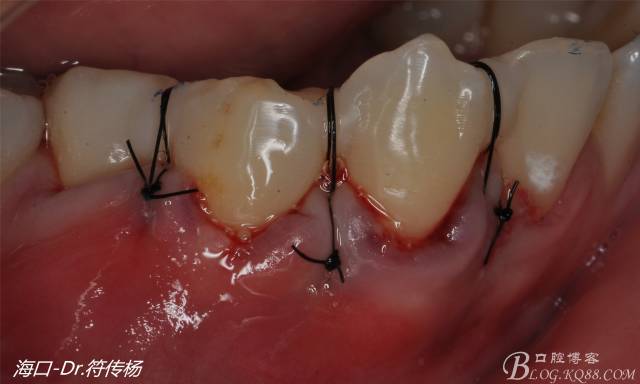

腭部使用水平懸吊縫合更利于壓迫止血

受植區(qū)建議使用雙交叉垂直懸吊縫合術(shù)來固定結(jié)締組織并能讓齦瓣更貼合根面利于術(shù)后一期愈合